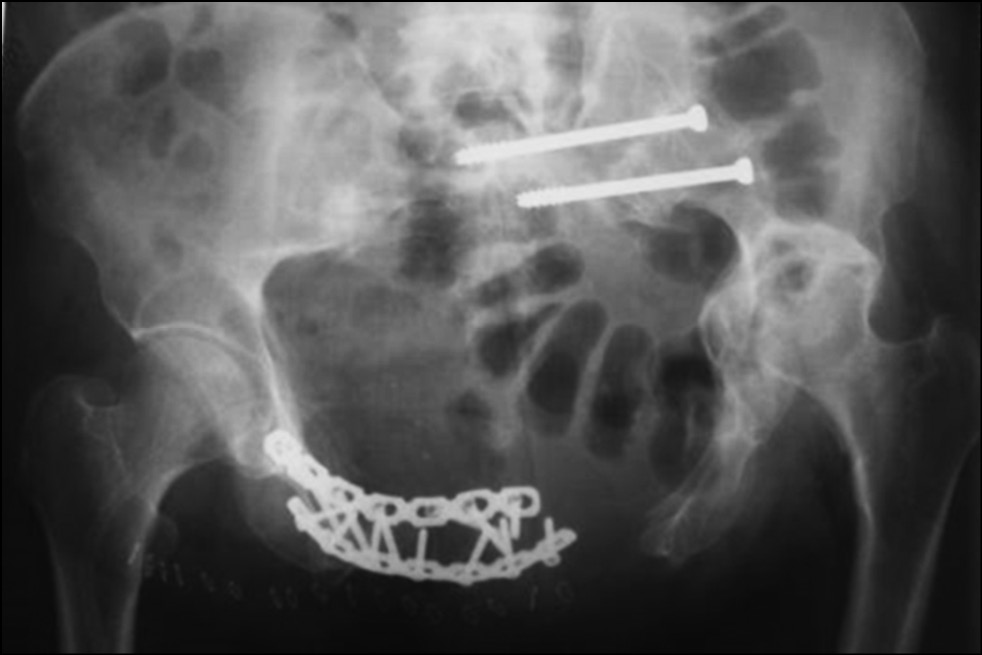

После низведения левой половины таза на втором этапе нами выполнен металлодез переднего полукольца таза двумя реконструктивными пластинами и произведена фиксация левого крестцово-подвздошного сочленения двумя канюлированными винтами (рис. 7, 8).

Рис. 7. Обзорная рентгенография таза после операции

Fig. 7. Plain radiography of the pelvis after surgery

Рис. 8. Каудальная рентгенография таза. Проекция in-let

Fig. 8. Caudal radiography of the pelvis. In-let projection